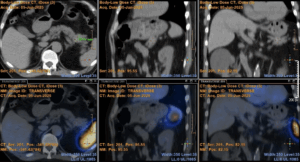

Abdominal MRI confirmed a solid nodular lesion in the pancreatic tail, with 30x20mm, with a pattern identical to that of the spleen. To exclude an ectopic intrapancreatic accessory spleen, a 99mTc-labelled red blood cell (RCR) scintigraphy was performed, but the pancreatic tail lesion did not show any radiopharmaceutical accumulation suggestive of splenosis (Fig. 2).

Figure 2. 99mTc-labelled RBR scintigraphy: No radiopharmaceutical accumulation the pancreatic tail.